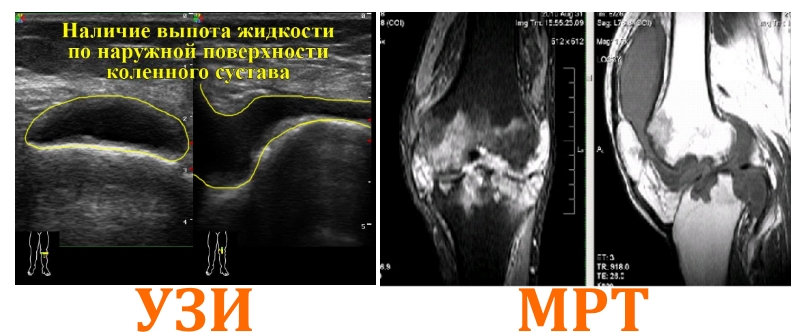

- Ультразвуковое исследование (УЗИ) помогает выявить воспалительные процессы в колене, определить объем жидкости в суставной полости и оценить состояние хрящевой ткани, связок, сухожилий, мышц и менисков. УЗИ является наиболее подходящим методом для диагностики тендинита, артрита, бурсита и гонартроза.

- Магнитно-резонансная томография (МРТ) позволяет обнаружить повреждения хрящевых и мягких тканей, таких как связки, мышцы и сухожилия. Этот метод помогает выявить микроповреждения, отеки и кровоизлияния, а также диагностировать опухоли на ранних стадиях, миодистрофию Гланцмана, аномалии сосудов и воспаление нервных стволов.

Врачи отмечают, что выбор между УЗИ и МРТ коленного сустава зависит от конкретной клинической ситуации. УЗИ является быстрым и доступным методом, который позволяет оценить состояние мягких тканей, связок и суставной жидкости. Этот метод особенно полезен для диагностики травм и воспалительных процессов. Однако его информативность ограничена при исследовании костных структур и глубоких тканей.

С другой стороны, МРТ предоставляет более детальную картину, позволяя визуализировать как мягкие, так и твердые ткани. Этот метод особенно эффективен для диагностики повреждений менисков, хрящей и других структур, которые могут быть не видны на УЗИ. Тем не менее, МРТ требует больше времени и ресурсов, а также может быть менее доступным.